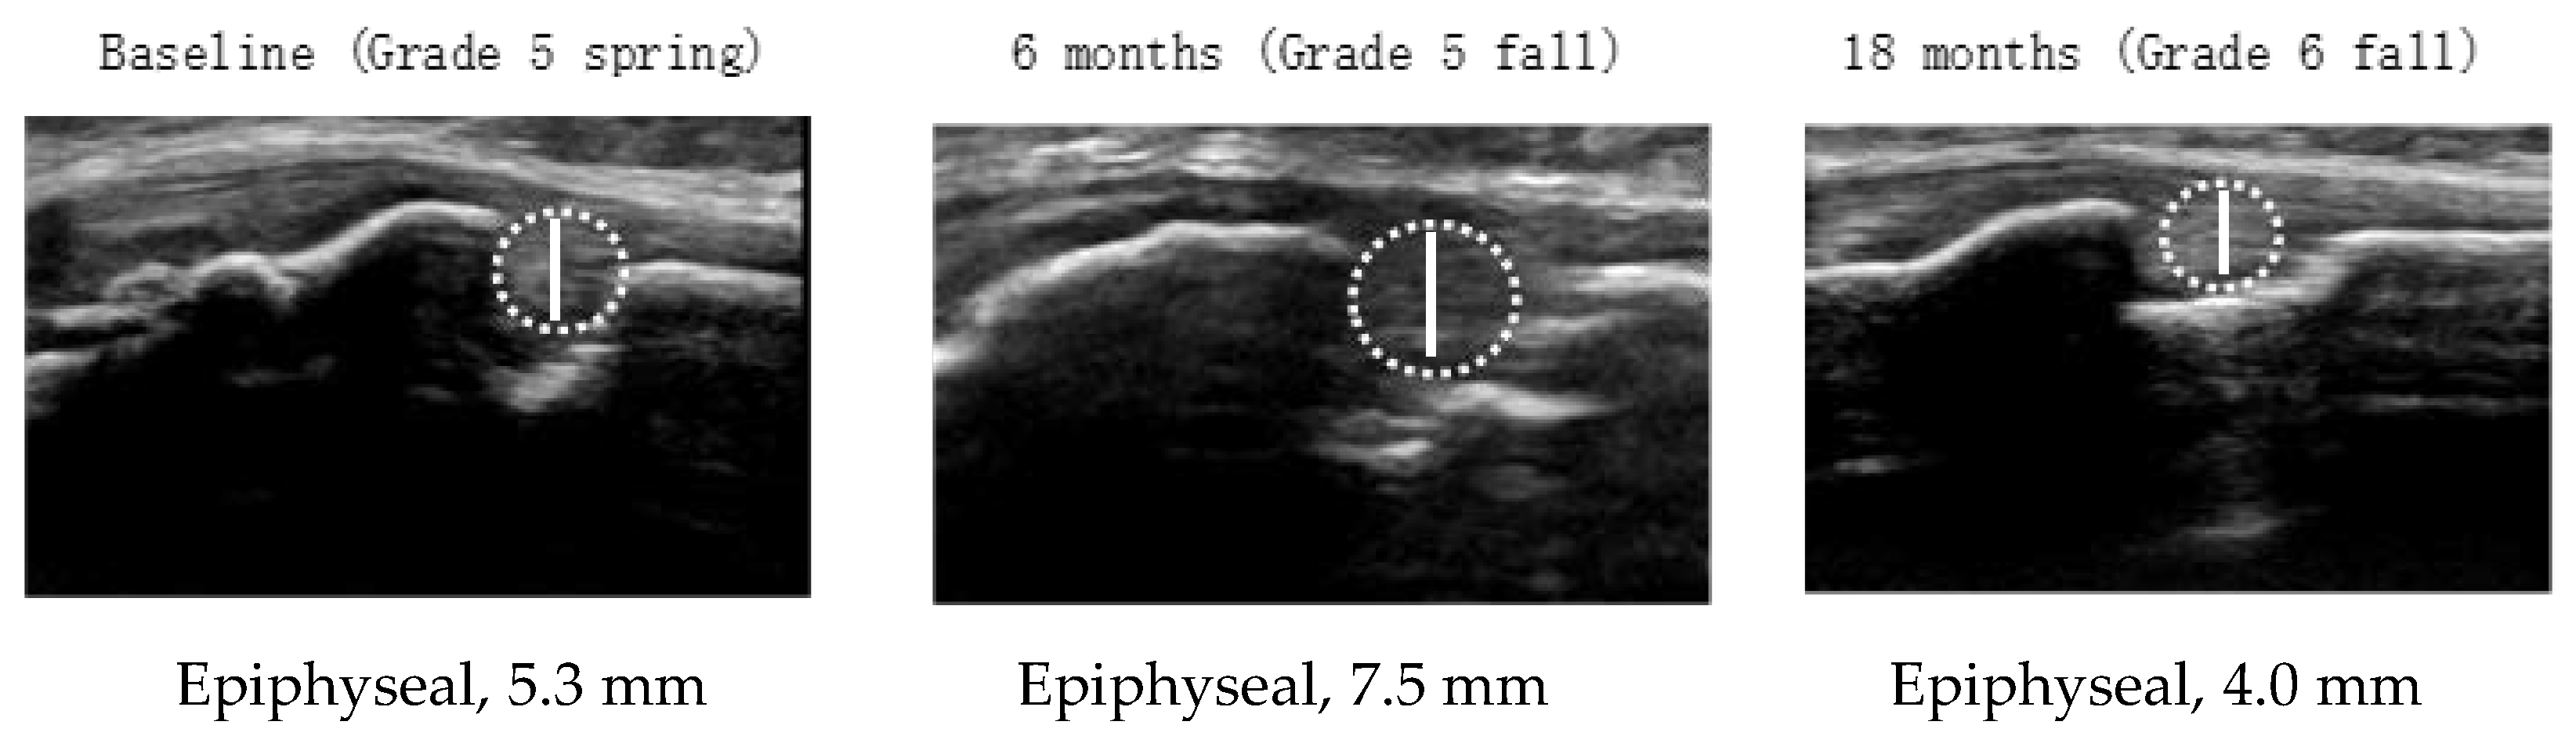

| Girls (n = 16) | Base Line a Grade 5 Spring | 6 Months b Grade 5 Fall | 18 Months c Grade 6 Fall | p-Value # | Multiple Comparisons ## |

| Demographic characteristics | |||||

| Age (y) | 10.1 ± 0.3 | 10.5 ± 0.5 | 11.6 ± 0.5 | <0.001 | a < b **, a < c **, b < c ** |

| Height (cm) | 139 ± 5 | 142 ± 5 | 149 ± 4 | <0.001 | a < b **, a < c **, b < c ** |

| Weight (kg) | 32.5 ± 5.5 | 34.8 ± 5.9 | 40.7 ± 6.0 | <0.001 | a < b **, a < c **, b < c ** |

| Appearance of menarche | 1 (6) | 2 (13) | 9 (56) | ||

| Sports club affiliation | 11 (69) | 12 (75) | 10 (63) | ||

| Osgood–Schlatter disease | 0 | 1 (6) | 1 (6) | ||

| Tibial tuberosity maturity stages | |||||

| Cartilaginous stage | 2 (13) | 0 | 0 | ||

| Apophyseal stage | 3 (19) | 2 (13) | 0 | ||

| Epiphyseal stage | 11 (69) | 14 (88) | 16 (100) | ||

| Bony stage | 0 | 0 | 0 | ||

| Cartilage thickness (mm) | 5.3 ± 1.2 | 5.4 ± 0.9 | 4.9 ± 0.7 | 0.282 | |